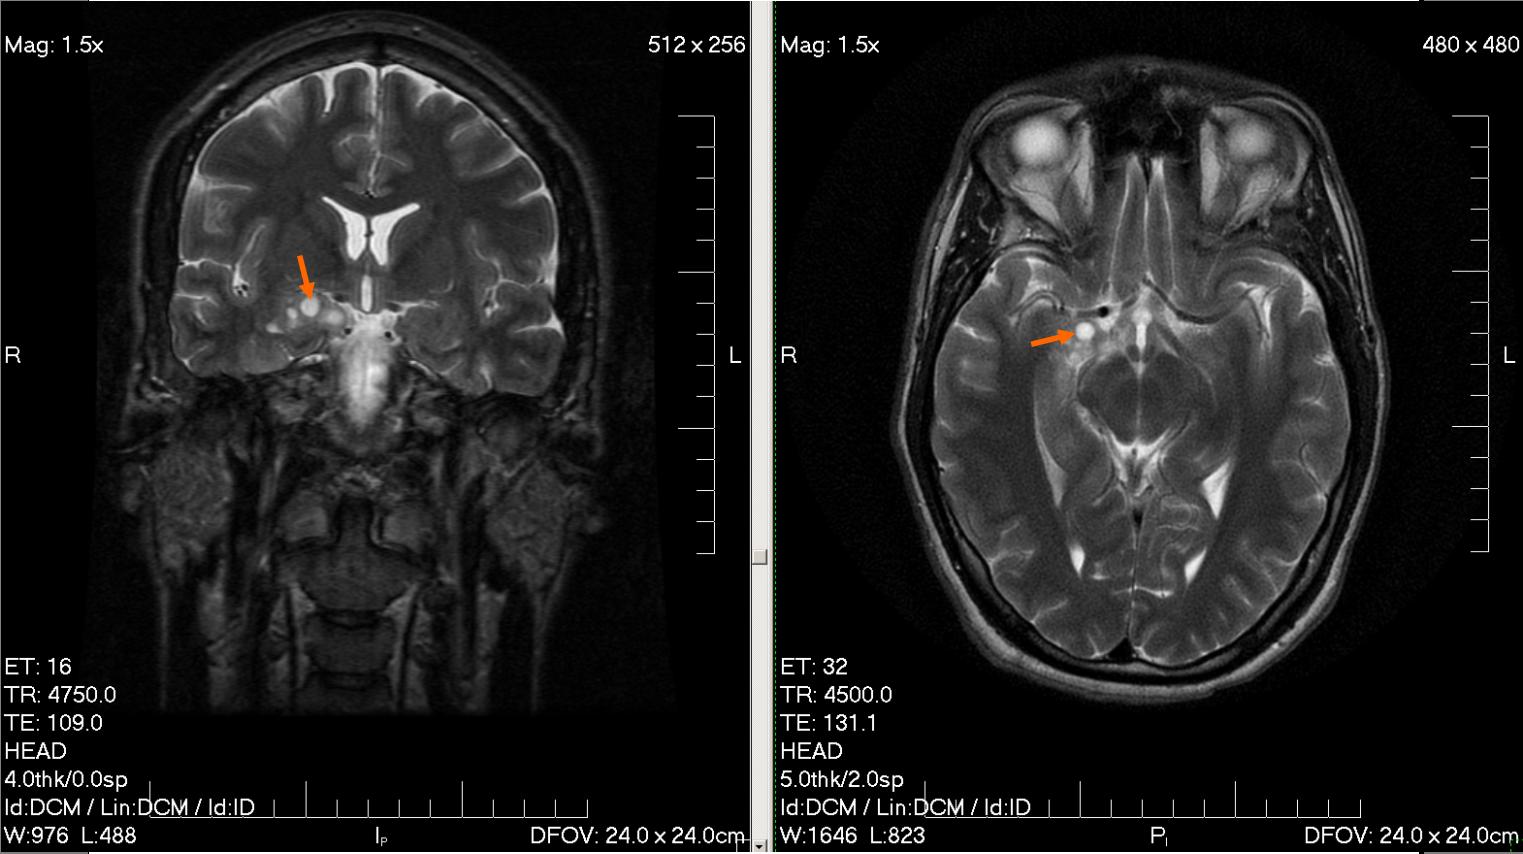

К обязательным методам обследования относятся определение активности сухожильных рефлексов, проверка тактильной и болевой чувствительности. Диагностические мероприятия могут быть расширены в зависимости от жалоб больного и с целью дифференциальной диагностики. Так, например, если больной отмечает нарушения координации, следует провести пальце-носовую пробу, проверить устойчивость в позе Ромберга. Если возникает подозрение на опухоль мозга, то больной направляется на компьютерную (КТ) или магнитно-резонансную томографию (МРТ). МРТ с контрастным усилением является «золотым стандартом» в диагностике опухолей головного мозга. При обнаружении на томограмме объёмного образования решается вопрос о госпитализации больного в специализированный стационар.

После поступления в онкологический диспансер проводится ряд обследований с целью решить вопрос о тактике лечения данного больного, требуется ли ему хирургическое вмешательство и, если требуется, то как он его перенесёт, целесообразно ли его стационарное лечение. Проводится повторная КТ или МРТ головного мозга. Определяются режимы и дозы лучевой и химиотерапии, картируется опухоль, определяются её границы, размеры, точная локализация. Если больному показано хирургическое лечение, то берут биоптат опухоли и производят её гистологическую верификацию с целью подбора оптимального режима последующей терапии. Также, препарат ткани опухоли может быть получен путём стереотаксической биопсии.